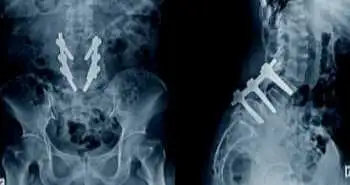

Efficacy of duloxetine to treat low back pain patients who had posterior spinal fixation

A randomized, placebo-controlled trial was performed to explore the efficacy of duloxetine on pain severity and quality of life in 50 patients with chronic low back pain who were candidates for posterior spinal fixation.

Participants were divided into either the duloxetine group or placebo group. The visual analogue scale (VAS), Short-form-36 Health Survey (SF-36), and Hamilton questionnaires were filled before surgery and after six weeks.

Vital differences were noted among groups for the VAS and the verbal analogue scale. Compared to  placebo group, subjects in the duloxetine arm had greater visual and verbal pain scores. Prior to the intervention, both the cohorts displayed a vital difference in quality of life. Considerable differences in Hamilton Anxiety Rating (HAR) Scale between groups were witnessed. Following the intervention, only the HAR scale, general health and bodily pain subscales of quality of life displayed a vital difference between the arms.

Only in the duloxetine group, a vital difference was noted between pre and post intervention in the HAR scale. Regarding the quality of life, the subscales of the total score of quality of life, physical pain, and physical and emotional role in both arms were remarkably distinct after therapy. The subscales of general health and physical function were considerably different only in the duloxetine arm after the therapy.

Using duloxetine in individuals who had spinal surgery, can help to mitigate back pain. Further studies with longer sample size and treatment duration are needed.